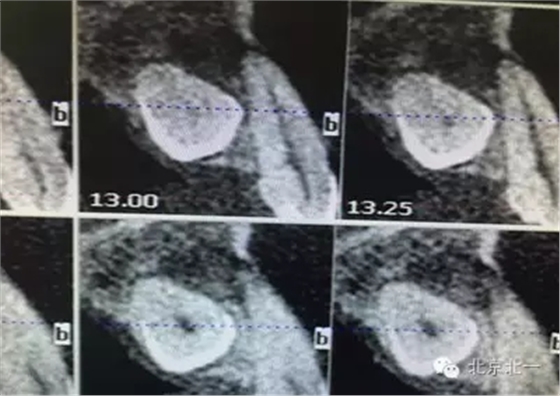

患者種植一月后種植區(qū)不適,偶有疼痛來(lái)院拍片發(fā)現(xiàn)23埋伏牙,與種植體相鄰,如圖一、二、三、四所示。